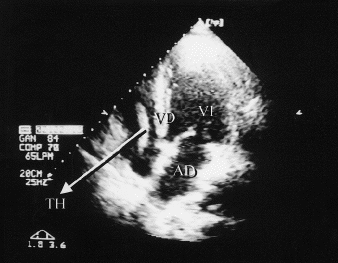

Al octavo día se realizó ecocardiograma que puso de manifiesto una imagen de aspecto fusiforme, dirigida desde zona de la vena cava superior hacia la válvula tricúspide (sobrepasándola), con consistencia de trombo y bastante móvil (60 ×8 mm) (fig. 1).

Fig. 1. TH: trombo cardíaco; VD: ventrículo derecho; VI: ventrículo izquierdo; AD: aurícula derecha.